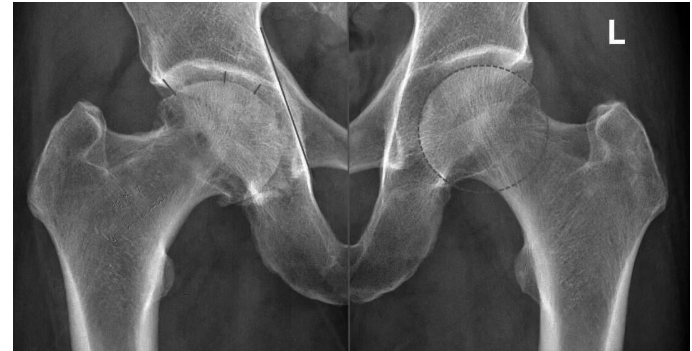

股骨头坏死发展到一定阶段,会出现“裂缝”(软骨下骨折)、“空洞”(囊性变)等。其实,股骨头内有“空洞”,不一定意味着坏死。下面,我举例说明。 病例 这是一位男性患者,今年67岁,6个月前无明显诱因出现右髋部大腿内侧及右膝关节疼痛,劳累后疼痛加重。他到当地医院拍片。当地医院医生看了一下片子,认为是右侧股骨头坏死,遂让患者口服药物治疗。口服药物治疗1个月,患者的疼痛未见明显减轻,遂来到河南省洛阳正骨医院就诊。 我看了他的MRI(磁共振成像)片,发现和股骨头坏死的影像非常相似,但的的确确是骨性关节炎。 仔细看MRI片(图1),可见左侧股骨头(L)很圆,右侧股骨头不仅不圆且髋臼有内陷。将MRI片与CT片(图2)结合起来,可以明确诊断。CT片可见关节面下囊性变,关节间隙不等宽,周围还有骨质增生。 成人发育不良被确诊的年龄范围很大,早期可以在青春期剧烈运动后发现,也可以在40岁~50岁偶尔有疼痛时发现,当然多在60岁~70岁时被确诊——确诊时间取决于具体的头臼匹配、体重、工作性质、运动或劳动量。 当然,还可以换个思路来理解疼痛的机制——关节不稳定造成磨损增加,盂唇受到撞击后发生撕裂。 一般认为,50岁以下的髋关节发育不良可以考虑髋臼周围截骨术;50岁以上,对于疼痛无法通过保守治疗获得长期满意效果,首选关节置换治疗。 术中可见股骨头负重区软骨已经磨损殆尽,由此引起的疼痛是无法通过保守治疗解决的。 为什么骨性关节炎和股骨头坏死易混淆 骨性关节炎是一种以关节软骨退行性变和继发性骨质增生为特征的慢性关节疾病,多见于中老年人,女性发病率略高于男性。其核心病理改变是关节软骨的变性、破坏,导致关节疼痛、僵硬、肿胀及活动受限。 骨性关节炎与股骨头坏死在症状、影像学表现上存在诸多相似之处,这导致两者在临床诊断中容易混淆。 症状相似性 1.疼痛特点重叠 两者均可表现为髋部疼痛,且活动后加重。 骨性关节炎的疼痛多为渐进性,休息后可缓解。股骨头坏死引发的疼痛可能夜间明显,且休息后无法完全缓解。 2.关节功能影响 骨性关节炎和股骨头坏死均会导致活动受限、跛行等症状,且体格检查(如“4”字试验阳性)结果相似。 影像学表现交叉 1.早期影像学差异不明显 骨性关节炎的典型表现为关节间隙狭窄、骨赘形成。而股骨头坏死早期X线检查结果可能正常,需通过MRI检查发现骨髓水肿或“新月征”。 若仅做X线检查,可能漏诊早期股骨头坏死。 2.晚期病变相互关联 股骨头坏死晚期可因股骨头塌陷继发髋关节骨性关节炎。此时影像学表现可能同时具备两者特征,增加鉴别难度。 如何避免误诊 结合多种检查手段:X线联合MRI检查可提高诊断准确性。 关注疼痛细节:若有夜间痛、静息痛,更倾向于股骨头坏死。 详细询问病史:明确激素使用、饮酒史等关键信息。 (作者供职于河南省洛阳正骨医院)